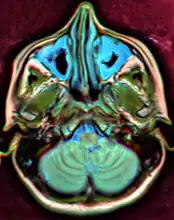

X-ray of left-sided maxillary sinusitis marked by an arrow. There is lack of the air transparency indicating fluid in contrast to the other side.